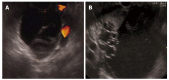

Cystic lesions of the pancreas are being diagnosed with increasing frequency, covering a vast spectrum from benign to malignant and invasive lesions. Numerous investigations can be done to discriminate between benign and non-evolutive lesions from those that require surgery. At the moment, there is no single test that will allow a correct diagnosis in all cases. Endoscopic ultrasound (EUS) morphology, cyst fluid analysis and cytohistology with EUS-guided fine needle aspiration can aid in this difficult diagnosis.